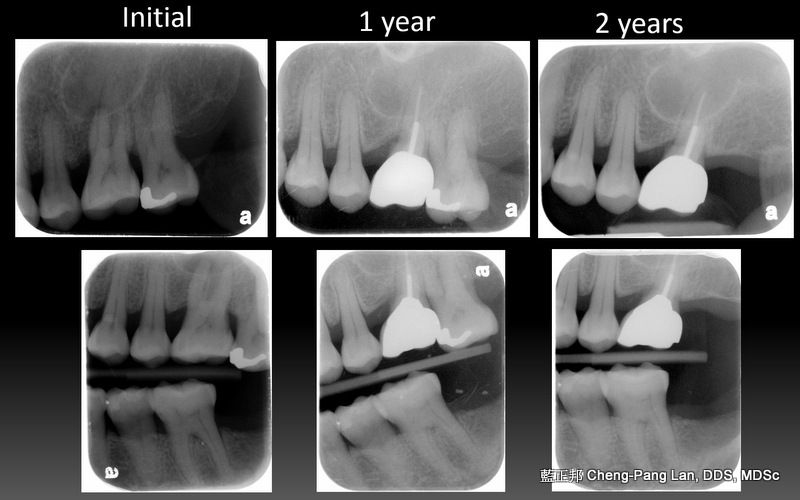

老師常常暗示著大家,implant與natural teeth之間,留下natural teeth比較好。這個我真的相信,在牙周病科的每一位學弟妹也都相信,甚至我相信週六在場的牙周病醫師都認同,但是大家有沒有想過,每隔週三一起開會的Prosthodontist、 Orthodontist都相信嗎?甚至,從實習醫師畢業就進入職場服務病人的學弟妹們,都相信嗎?